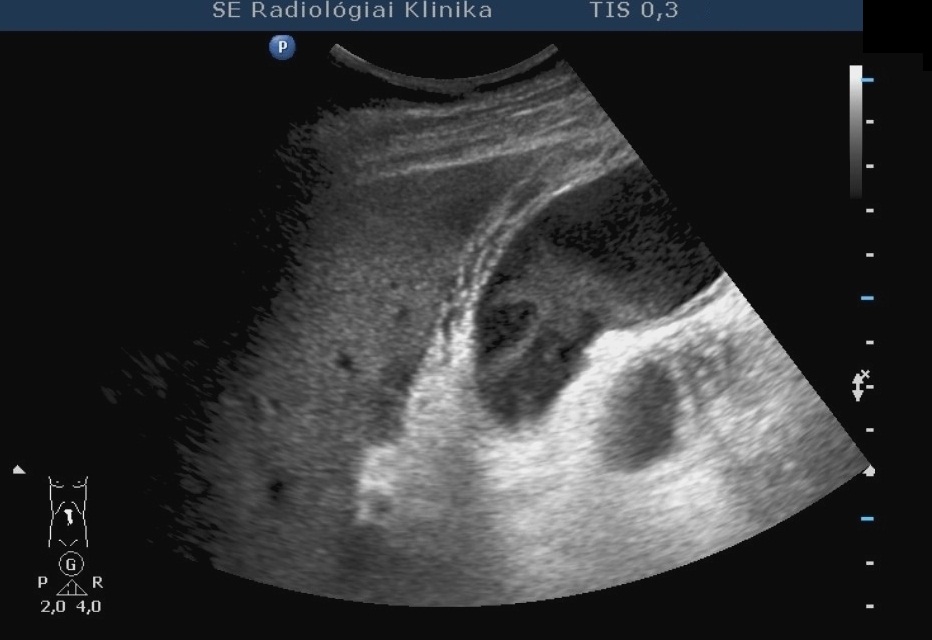

Besides these forms, metastases with mixed echostructure (containing both hyperechoic and hypoechoic areas) and cystic metastases with necrotic content can occur relatively often (Figure 24).

Figure 24: Metastases of a GIST tumour, US

The liver metastases of colorectal origin are usually characterised by a bit inhomogeneous hyperechoic structure sorrounded by a hypoechoic rim. (Figure 25)

Figure 25: Liver metastasis of rectal cancer, US

In the central area of bigger (4-6 cm in diameter) metastases necrosis can also develop as so called „target” form (or commonly called as bull’s eye sign).